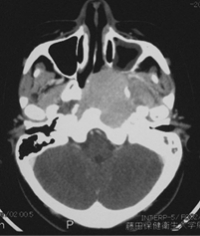

最も重大な中耳炎が、真珠腫性中耳炎です。鼓室から上の部分、”鼓膜の屋根裏部屋“のほうにかけて真珠腫といわれる「垢のかたまり」のようなものが出来てしまい、周囲をゆっくり破壊しながら徐々に進行します(先天性のものなど、例外もあり)。鼓膜や、鼓膜の上側の骨がえぐれて、そこから病変が奥にすすんでいきます。この部分の骨の中には、聞こえやバランスの機能、顔を動かす神経などとても大事なものが組み込まれていますから、放置するとこれらが破壊されてしまい重大なことになります。

上のほうに行くと脳の入っている床の部分の骨(頭蓋底)が抜けおちてしまい、脳の神経の障害の原因になったりすることもあります。当科では、非常に細かい部分まで撮影できる最新のCTなどによって術前に精査を行い、手術によって病気をしっかり取り去り、本来の聞こえの構造と鼓膜をしっかり作り直す手術(鼓室形成術)を行います。手術は繊細で時間がかかる作業で、入院が必要です。手術後は削った空間にゴミや膿がたまりやすくなったりすることもありますので、定期的に耳の中をケアしていく作業を行います。手術の方法は、病状によっても異なりますので、その都度相談させていただき決定してまいります。